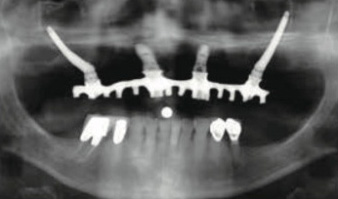

| 翼状突起インプラント | ザイゴマインプラント | |

| 可能な部位 | 一番奥の歯(7番・第二大臼歯) | 一番奥から2、3本目(5番第二小臼歯、6番第一大臼歯) |

| 術後レントゲン(上顎)の一例 | ![]() |

![]() |

| ノーベルガイドの利用 | 可 (メスで切開しない) |

不可 (メスで切開する) |

| 傷口の大きさ | 小さい | 大きい |

| 手術時間 | 短い | 長い |

| 麻酔 | 局所麻酔(通常のインプラントと同じ) | 静脈麻酔 |

| リスク | 腫れ、痛み | 腫れ、痛み、上顎洞炎、失明 |

| 術後の感染リスク | 通常のインプラントと同程度 | 高い インプラント体が骨と粘膜の間に位置するため感染症を起こしやすい |

| 歯肉からインプラントが出る場所 | 本来の歯と同じ | 本来の歯より内側なので磨きにくい事がある |

| インプラントの長さ | 8〜20mm | 35〜55mm |